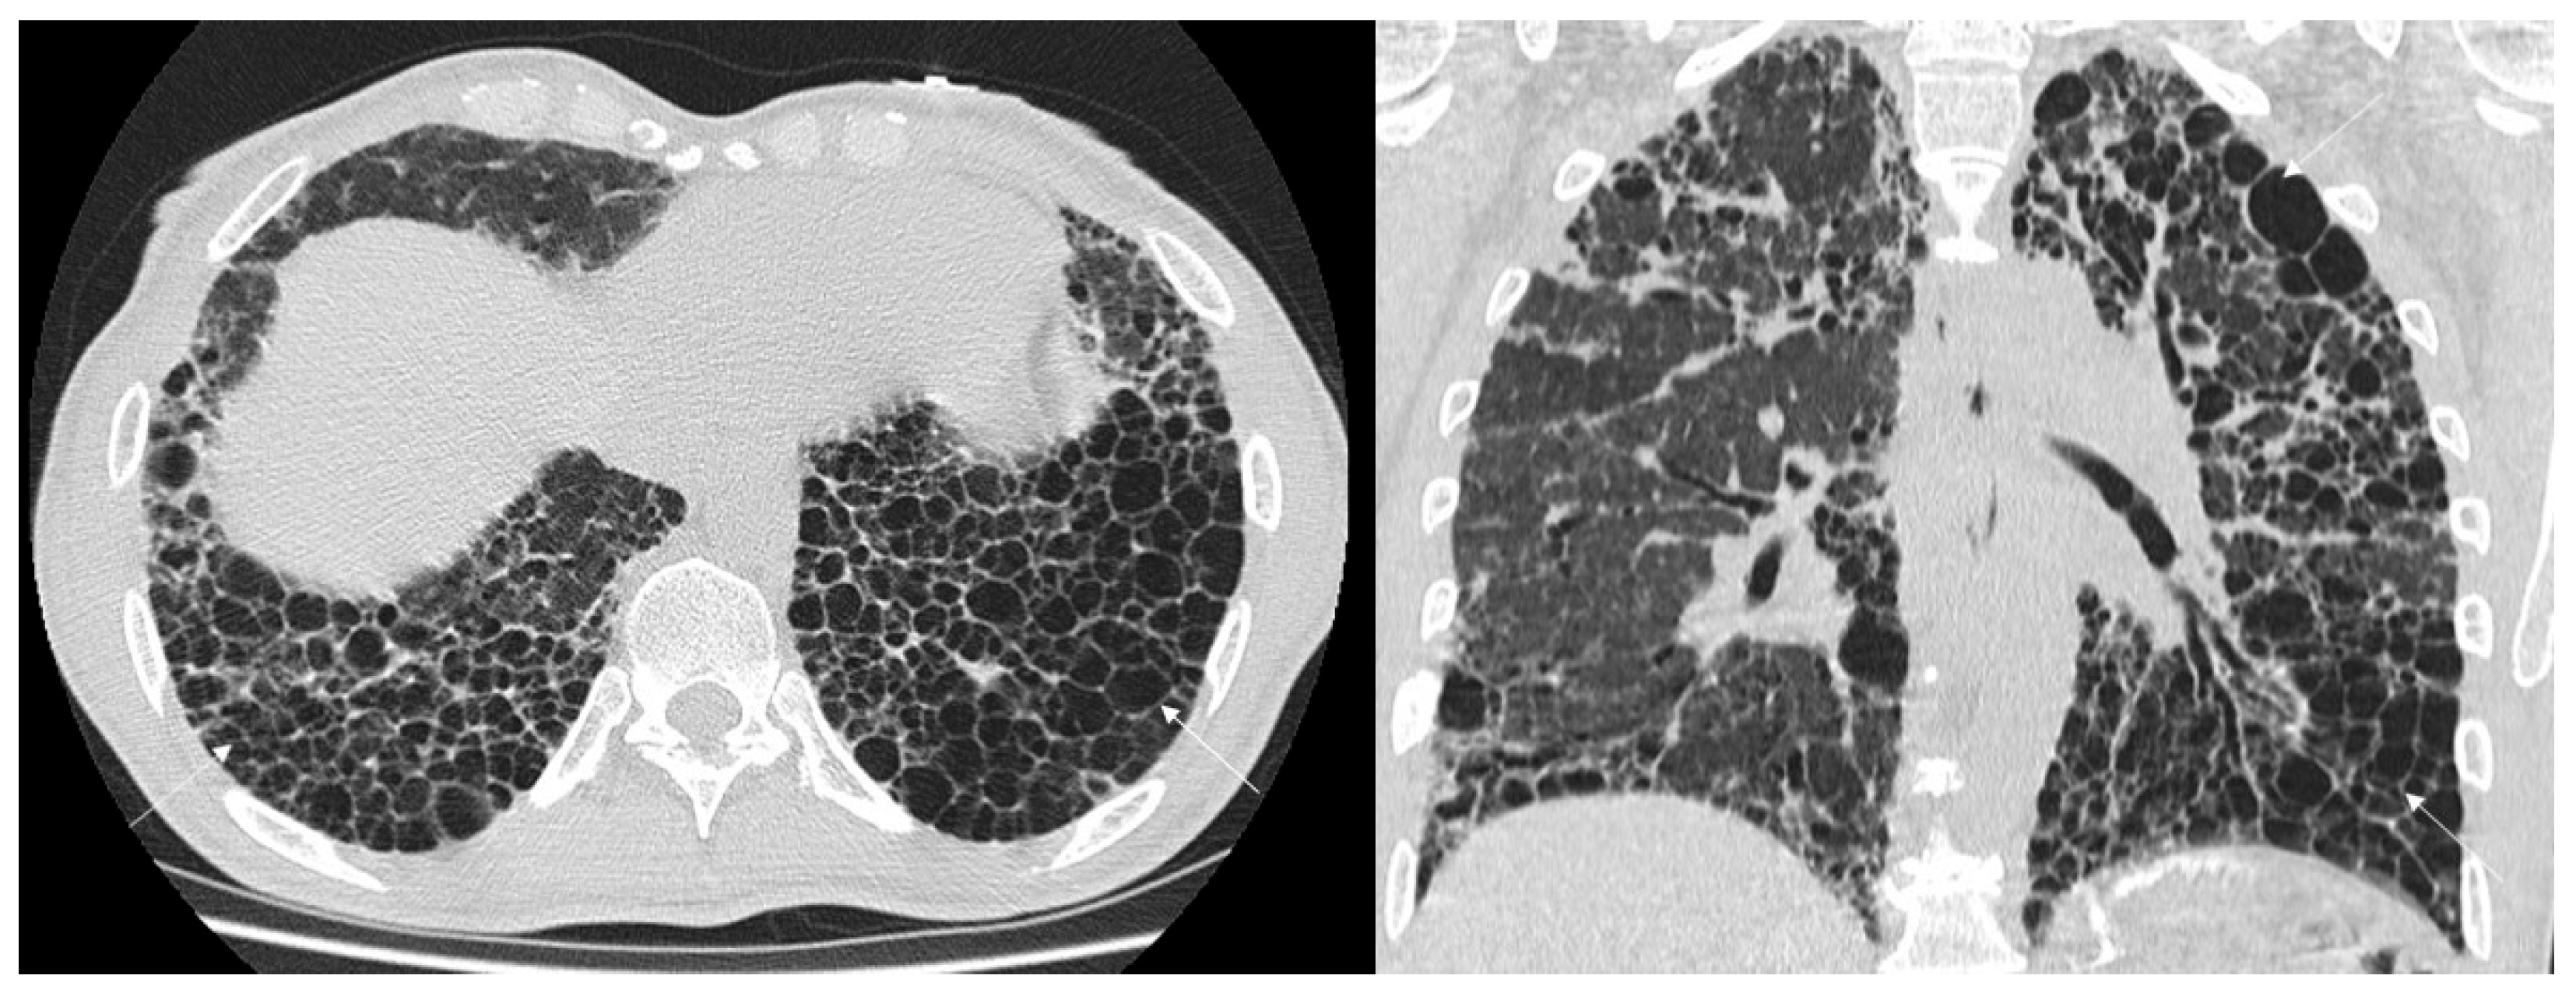

Other more specific fibrosis patterns– including macro/micro honeycombing, exuberant honeycombing (Figure 2), symmetric/asymmetric involvement of abnormalities, the “anterior upper lobe sign” (Figure 3), the “four corner sign”, the “wedge-shaped” distribution (Figure 4), anterior predominance of bronchiectasis (which means i.e., parallel bronchiectasis in the lingular or middle lobe)—were also assessed listed and evaluated. Microcystic and macrocystic honeycombing have been classified according to the definition reported in literature (macro for cystic spaces exceeding 4 mm in diameter) [18]; traction bronchiectasis were scored as follows: mild (=1), moderate (=2) and severe (=3), according to articles published in literature by Walsh et al. [19,20] and Baratella et al. [21]. Lastly, the radiologists analysed the presence of mediastinum abnormalities, such as (i) esophageal dilation; (ii) enlarged size of lymphatic nodes; (iii) pulmonary/aortic ratio. Occasional findings, not necessary directly related to the fibrotic UIP pattern, were also annotated documented by radiologists.

Figure 2. High-resolution computed tomography (HRCT) of the chest in axial (left) and coronal (right) views showing exuberant honeycombing, characterized by extensive, confluent subpleural cystic airspaces with well-defined walls and similar diameters, predominantly in the lower lobes and posterior regions.